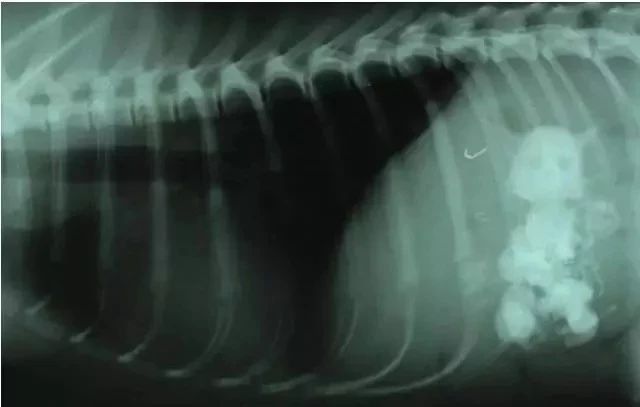

这只狗狗竟然吞下了一只猫......

是的,是只猫!X光影像下狗狗肚子里真的蹲着一只猫。

事实上,这货吞下了好几只猫。

有宠物医院专门PO出了一些X光影像来提醒铲屎官注意狗狗异食行为,看看它们吞下的东西简直让人瞠目结舌。